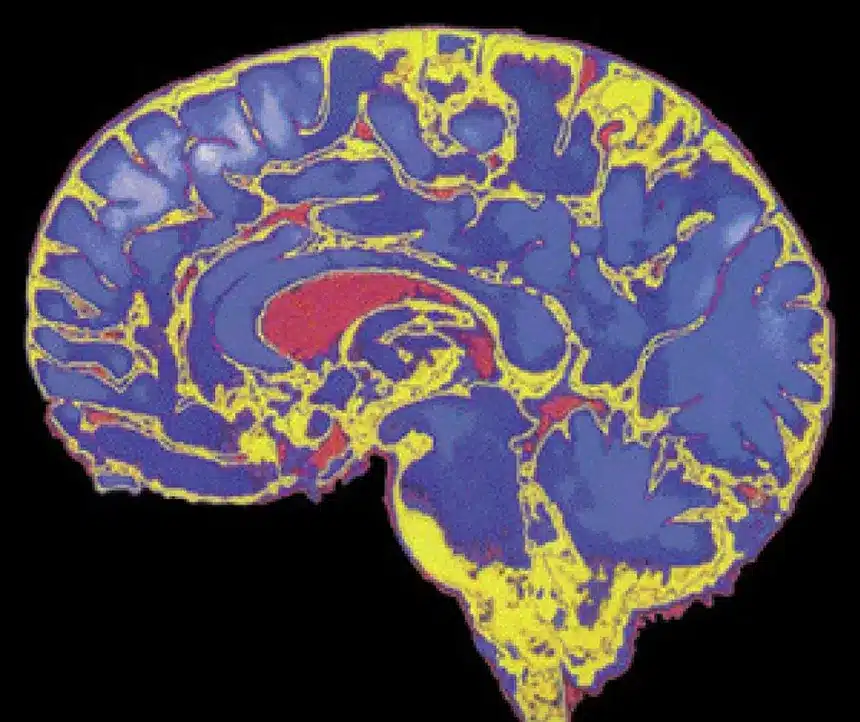

El epicentro de este descubrimiento se encuentra en la corteza prefrontal, la región del cerebro responsable de las funciones ejecutivas, como la toma de decisiones, el control de impulsos y la comprensión de las consecuencias. Los estudios de neuroimagen han demostrado que esta área no alcanza su pico de conectividad y mielinización sino hasta bien entrada la tercera década de vida. La mielina, una sustancia grasa que recubre las neuronas para acelerar la transmisión de impulsos eléctricos, se deposita de manera gradual de atrás hacia adelante en el cerebro, dejando la “estación de mando” frontal como la pieza final del rompecabezas madurativo.

Este retraso en la maduración biológica tiene implicaciones profundas en la forma en que los adultos jóvenes procesan las emociones y evalúan el riesgo. Mientras el sistema límbico, encargado de las respuestas emocionales y el placer, se activa plenamente desde la pubertad, la falta de una corteza prefrontal totalmente integrada crea un desequilibrio neurobiológico. Esta brecha temporal entre el impulso emocional y el freno racional explica por qué la transición a la estabilidad emocional no ocurre de forma repentina al cumplir la mayoría de edad legal, sino que es un proceso fluido que se extiende mucho más allá de lo que se creía anteriormente.